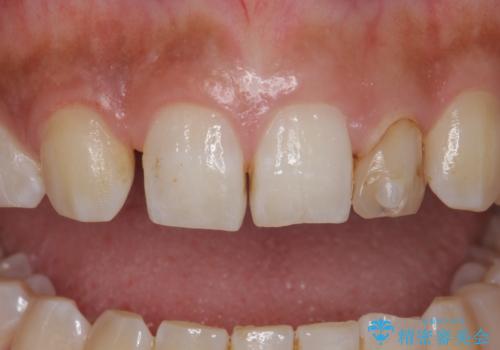

変色した前歯をキレイにしたい ジルコニアクラウンでの修復

- 左上の前歯の変色が気になるとのことで来院されました。

もともと小さい歯(矮小歯)に樹脂が盛り足されている状態でした。

今後の変色をなくすために樹脂ではなくセラミックでの治療を行います。

- 左上2:仮歯+ジルコニアクラウン/11,000円+110,000円費用は治療当時の料金となります

セラミックでの治療をすることにより今後の変色を抑えることができます。

色・形ともに改善することができ大変喜んでいただけました。